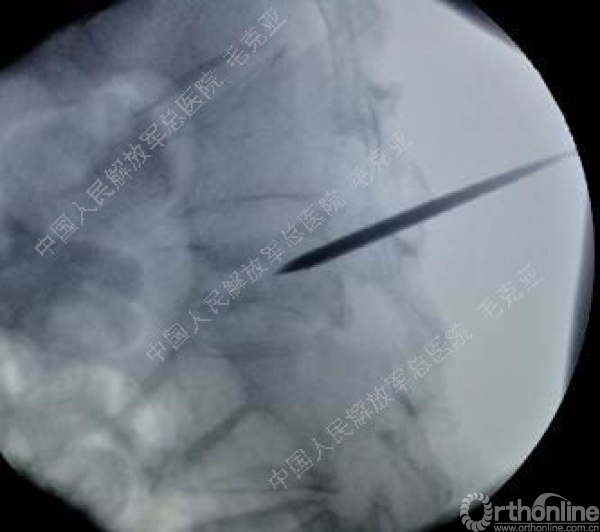

导语:随着社会老龄化的不断加速,骨质疏松性椎体压缩骨折作为一种普遍存在的老年骨科疾病已经成为现今骨科界的一个热点话题。传统的保守疗法治疗效果不佳,而现有的椎体增强技术又具有多种风险和缺陷。针对这种现状,中国人民解放军总医院毛克亚教授提供了一种新的解决方法。